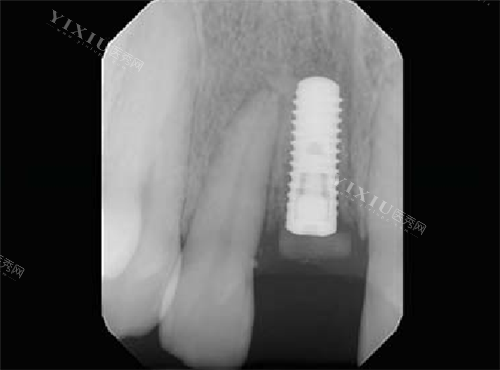

士卓曼的种植体分级主要基于两个核心参数:材料学特性和表面处理技术。材料方面从四级纯钛发展到钛锆合金复合材质;表面处理技术则从基础喷砂酸蚀工艺升级至分子级亲水涂层工艺。这种分级方式体现了从常规修复到复杂病例解决方案的技术演进路径。

采用符合ASTM F67标准的四级纯钛材料,通过喷砂酸蚀技术形成3-5μm的表面孔隙率。这种微米级结构可增加约40%的骨接触面积,但需要较长的骨整合周期。

TiZr合金通过冷加工工艺使屈服强度达到980MPa,弹性模量更接近皮质骨。其断裂韧性值(KIC)达60MPa·m¹/²,是纯钛材料的2倍以上,能有效抵抗咬合疲劳应力。

在美学区应用时,其0.8mm的更小径值可实现穿龈轮廓的自然过渡。全口重建病例中,4mm短植体也能提供足够的初期稳定性,突破传统种植的骨量限制。